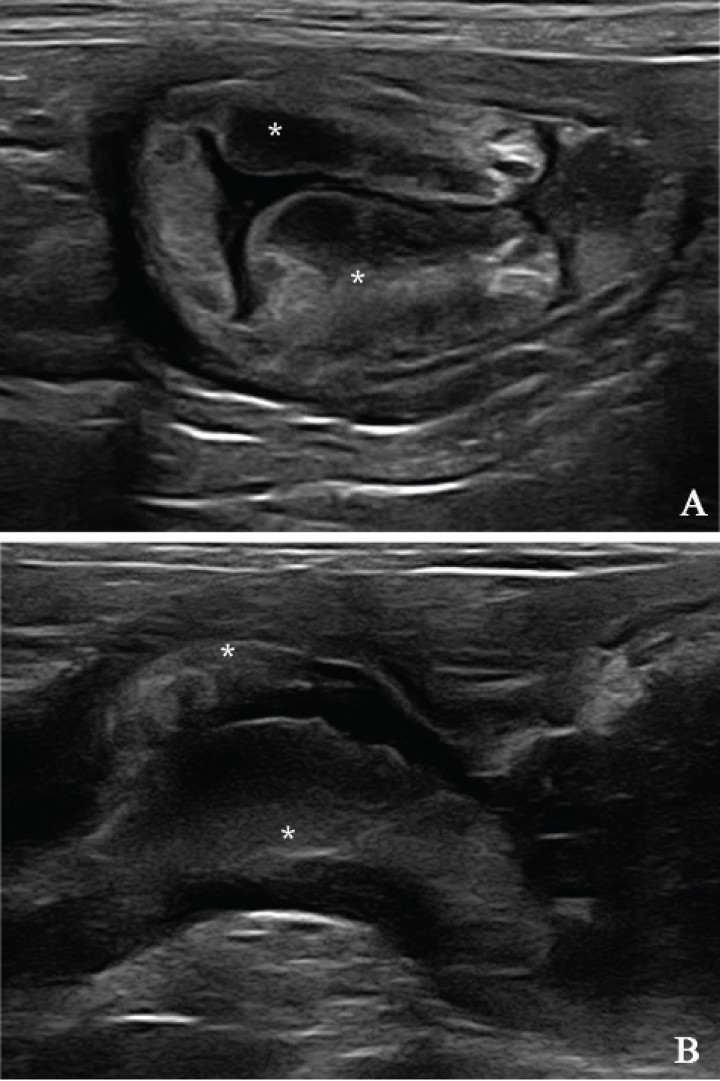

Por todo ello, en este caso se decidió realizar una ecografía abdominal en la que se evidenció un estómago muy distendido con contenido líquido y restos de alimento, no visualizándose movimiento peristáltico durante un periodo de observación de cinco minutos, indicando un retraso en el vaciado gástrico. Al evaluar las capas de la pared del estómago a nivel del antro pilórico se observó un engrosamiento de la pared (1,6 cm de grosor) que afectaba a ambos lados de forma asimétrica y hacía protusión hacia la luz gástrica (Fig. 2) (ver vídeo 1). La pared gástrica mantenía la estratificación de sus capas, estando engrosada la mucosa. El resto de los órganos abdominales no presentaba ninguna alteración ecográfica.

<p>Imagen ecográfica de la zona del antro pilórico. (A) Corte transversal. (B) Corte longitudinal. Se visualiza un engrosamiento asimétrico de la pared (*) que protruye hacia la luz gástrica.</p>

Figura 2

Imagen ecográfica de la zona del antro pilórico. (A) Corte transversal. (B) Corte longitudinal. Se visualiza un engrosamiento asimétrico de la pared (*) que protruye hacia la luz gástrica.

En base a los hallazgos ecográficos, el diagnóstico más probable fue de hiperplasia/hipertrofia de la mucosa gástrica, siendo el menos probable la presencia de una neoplasia. Aunque el diagnóstico definitivo solo se obtiene mediante el examen histopatológico de una muestra de la pared del antro pilórico.